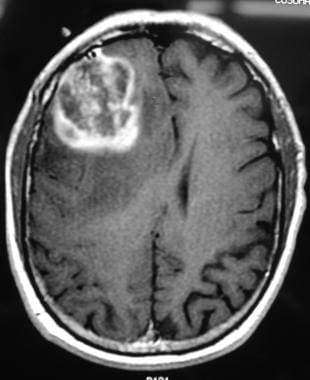

多形性膠質(zhì)母細胞瘤的影像學診斷

膠質(zhì)母細胞瘤(惡性膠質(zhì)瘤)是較常見的成人惡性腦腫瘤,20%的原發(fā)性腦腫瘤是多形性膠質(zhì)母細胞瘤。多形性膠質(zhì)母細胞瘤(GBM惡性神經(jīng)膠質(zhì)瘤)是星形細胞瘤的較高級形式,約占全部腦星形...